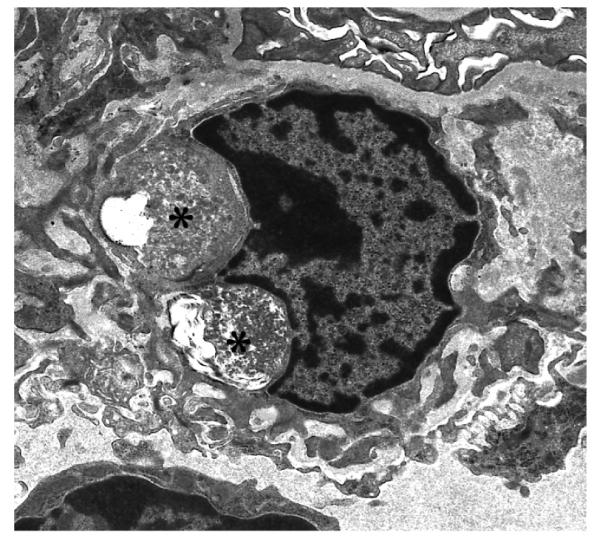

In glomeruli, visceral and parietal glomerular epithelial cells and occasional mesangial cells had well circumscribed membrane bound accumulation of GRODs by 3 – 5 months of age and the amount of storage increased progressively in 3, 5 and 7 month old PPT1 −/− mice (Figure 1A and B, Table 1). Tubular epithelial cells in PPT −/− mice had no osmiophilic storage at any age.

Fig. 1 A and B.

Glomerular visceral and parietal epithelial cells from a 5 month old (A) and Glomerular mesangial cell from a 7 month old (B) PPT −/− mouse have membrane bound electron-dense coarse granular cytoplasmic storage (asterix). (A and B: uranyl acetate-lead citrate, A 8,300X and B 6,600X magnification)